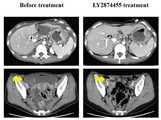

도 1a는 위암환자에서 LY2874455 치료 전과 후의 컴퓨터 단층촬영(CT) 이미지이고, 도 1b는 LY2874455 치료 14개월 후 상기 약물에 대한 내성이 유발되어 복막의 파종 및 폐쇄성 위 조직이 생긴 위의 이미지이다.

도 1a에 LY2874455의 치료 전과 후 상기 환자의 컴퓨터 단층촬영 사진을 나타내었으며, 도 1b를 통해 LY2874455 치료 14개월 후 LY2874455에 대한 내성이 유발된 조직을 확인할 수 있다.1A shows a computed tomography photograph of the patient before and after the treatment of LY2874455, and through FIG. 1B, tissues induced with resistance to LY2874455 after 14 months of LY2874455 treatment can be identified.